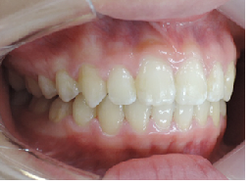

MEAW(マルチループ)を使用する事で、上顎前突(出っ歯)や咬合高径(咬み合わせの高さ)を改善して2年6ヶ月で非抜歯での治療で綺麗な歯並びになりました。

☆終了時

矯正治療後は後戻りが問題となりますが、歯を抜かないで治療しているため後戻りも最小限で済みます。